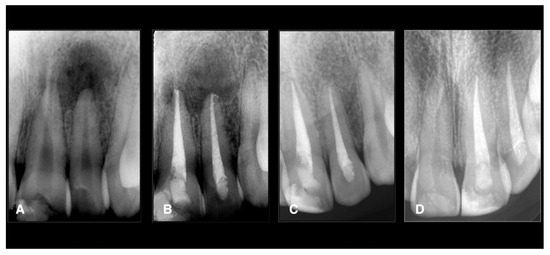

| All data Male: 55 Female: 35 Age: all the patients were between 20 and 45 years. Oral hygiene: 65 patients had good hygiene. Tobacco use: 10 patients used it. Teeth: 20 maxillary molars, 40 mandibular molars, 30 maxillary premolars. Intraoperative data collection Twenty teeth had sealer extrusions. The working length was respected in all teeth. Postoperative data collection Post-treatment symptoms were assessed two days after the treatment using a visual analogue scale (VAS; 0 and 10) Thirteen maxillary molars: 2 Seven maxillary molars: 1 Five mandibular molars: 4 Eighteen mandibular molars: 3 Ten mandibular molars: 2 Seven mandibular molars: 1 Sixteen maxillary premolars: 2 Twelve maxillary premolars: 1 Two maxillary premolars: 3 Total number: 90 teeth Two patients (2 teeth) did not come for the follow-up. Of the 88 teeth, 84 (95%) were healed, and four (5%) failed. Four teeth failed: 2 maxillary premolars and two mandibular molars (these teeth did not have sealer extrusion). One maxillary premolar failed with vertical root fracture. |

| Follow-up n = 88 | 84; 95.4 | 0; 0.0 | 0; 0.0 | 84 95.4 | 4; 4.6 | 0; 0.0 | 4; 4.6 |

| Maxillary molars | 20 | 7 (35.0) | 13 (65.0) | 0 (0.0) | 0 (0.0) | 19 (95.0) | 6 (30.0) | 0 (0.0) | 0 (0.0) |